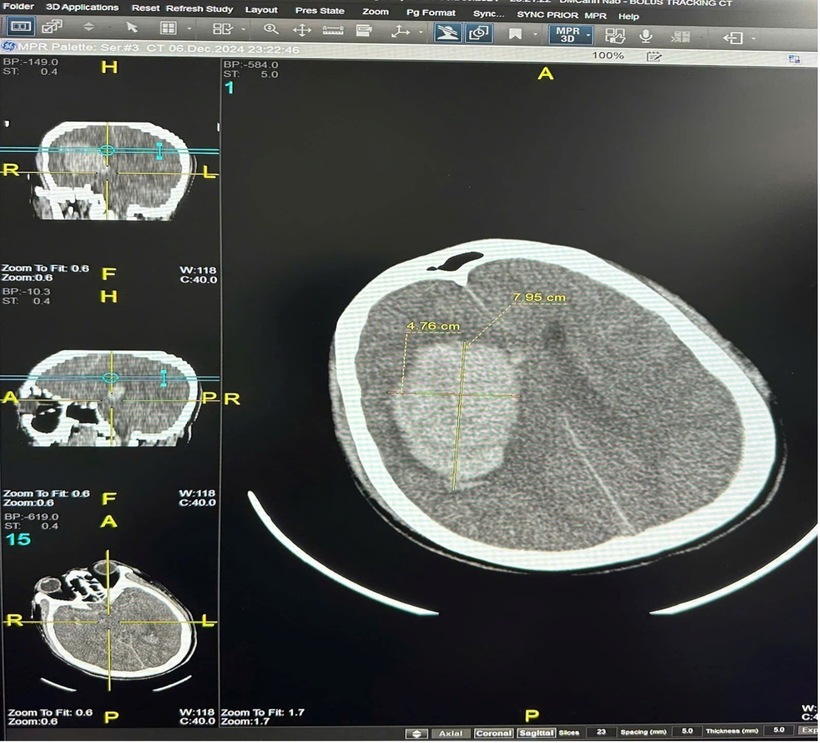

Trường hợp đầu tiên, đêm 6/12 khi bắt đầu đợt không khí lạnh gần đây nhất, bệnh nhân nam Đ.V.Đ (45 tuổi, Hà Nội) không có tiền sử bệnh lý, cấp cứu trong tình trạng hôn mê sau khi tắm khuya. Kết quả chẩn đoán cho thấy xuất huyết não với khối máu 90 cm³, và bệnh nhân buộc phải phẫu thuật mở sọ để giải ép áp lực não, hiện tại bệnh nhân vẫn phải điều trị tích cực, duy trì thở máy, tiên lượng rất nặng.

Hình ảnh phim CLVT của bệnh nhân Đ.V. Đ khối máu tụ bán cầu phải với thể tích khoảng 90 cm3. Ảnh: BVCC